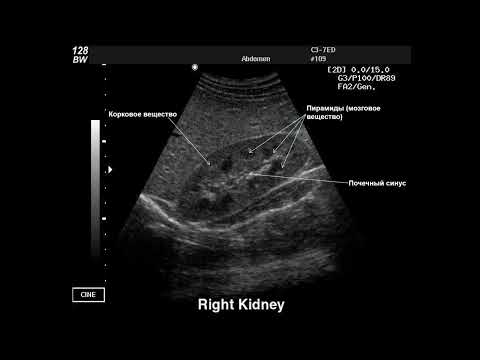

Как ультразвуковой аппарат Mindray Consona N8 показывает себя в урологии? В этом видео проведём исследование органов мошонки (яичек и придатков) и посмотрим, какие возможности прибор открывает в практике врача-уролога. Обычно на нашем канале выходят мастер-классы по эхокардиографии, УЗИ щитовидной железы, сосудов и нервов — это наиболее частые и доступные для демонстрации исследования. Сегодня мы расширим диапазон и протестируем аппарат в урологии. Клинический специалист компании MEDLIGA, преподаватель по ультразвуковой и функциональной диагностике учебного центра «Medtrain» Константин Князев выполнит исследование и продемонстрирует качество визуализации на линейном датчике L13-3N, возможности оптимизации изображения и функционал прибора, применимый в урологической практике. УЗИ аппарат Mindray Consona N8 на сайте MEDLIGA -

00:05 - Вступление. 00:25 - Исследование мошонки и придатков (справа). 04:30 - УЗИ мошонки и придатков (слева). 06:04 - Измерения и расчеты в отчете исследования. 06:54 - Итоги мастер-класса. Заключение. #medliga #mindray #узи #узимошонки #диагностика #медицина #мастеркласс